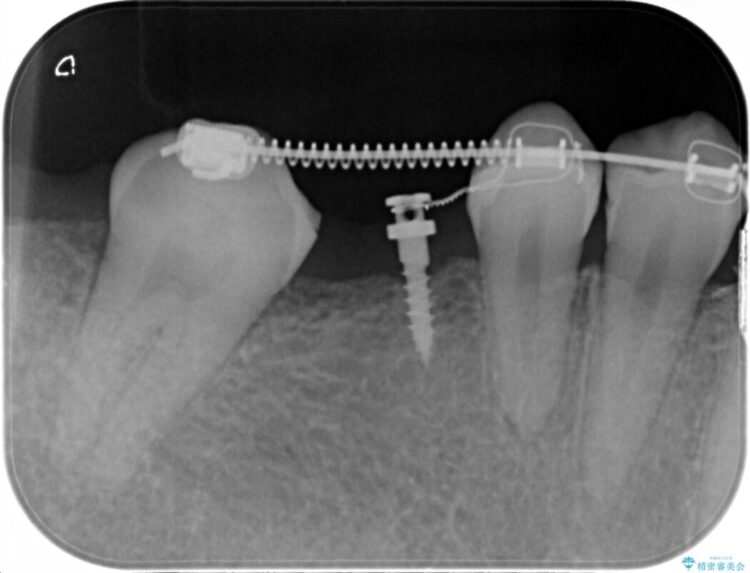

診査した結果、欠損した状態で長期間放置していたことが原因で最高峰の奥歯が欠けた部分に向かって傾斜してしまっていました。

この状態のままブリッジ治療へと進んでしまうと神経が露出する可能性が否定できないため、まずワイヤー装置による部分矯正で歯軸を通常位置へ戻してから補綴治療を行うこととしました。